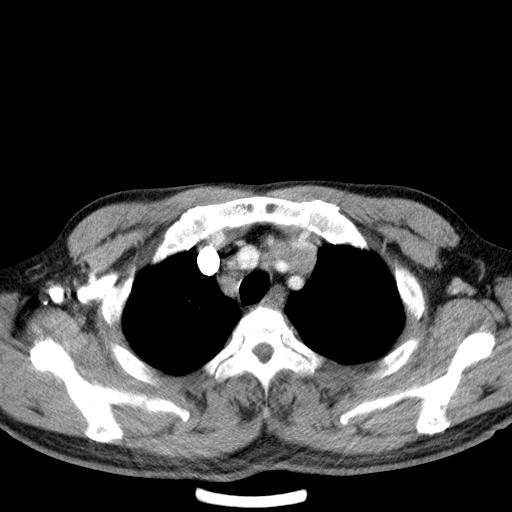

先行ct平扫,纵膈内多发软组织影,ct值约为36hu,以下为增强扫描和腹部平扫。

经典?纵膈多发肿大淋巴结。腹膜后未见异常。

淋巴瘤?胸腺瘤?

1)考虑淋巴瘤。2)双侧少量胸腔积液。